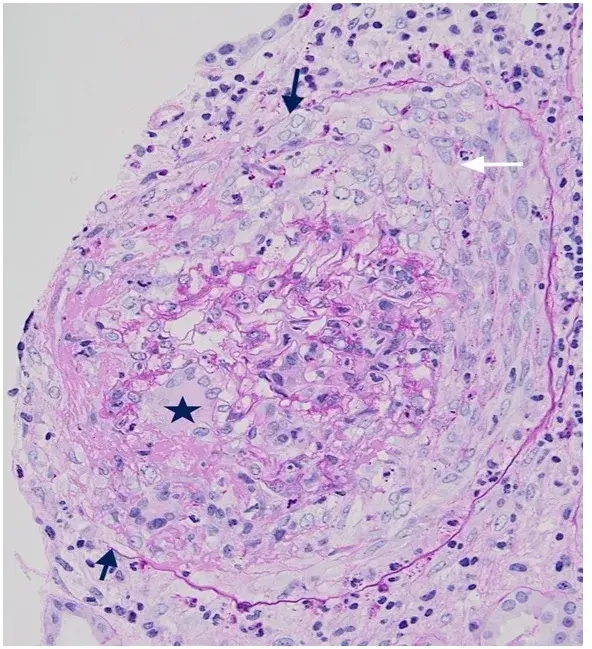

É possível identificar um glomérulo com quebra ruptura da MBG, com crescente celular no espaço de Bowman (seta branca), célula gigante multinucleada (estrela) e ruptura da cápsula de Bowman (seta preta) (PAS; 400×). PAS, ácido periódico-Schiff.

A biópsia renal revelou GN crescêntica necrotizante difusa sem hipercelularidade endocapilar. Alguns raros glomérulos continham células gigantes multinucleadas.

A avaliação da microscopia de luz pode ajudar na diferenciação de casos de **GN por anti-MBG** de casos **GN-ANCA**, já que na GN anti-MBG não observamos hipercelularidade endocapilar e pode ser identificado a presença de células gigantes multinucleadas, estas células gigantes multinucleadas resultam a natureza explosiva e a rápida destruição dos glomérulos observadas em anti-MBG

Desta forma, a presença de lesões crescentes temporalmente semelhantes e células gigantes multinucleadas na microscopia de luz (MO) pode ajudar no diagnóstico precoce.